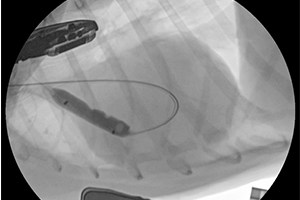

요도 스텐트 시술 중인 모습